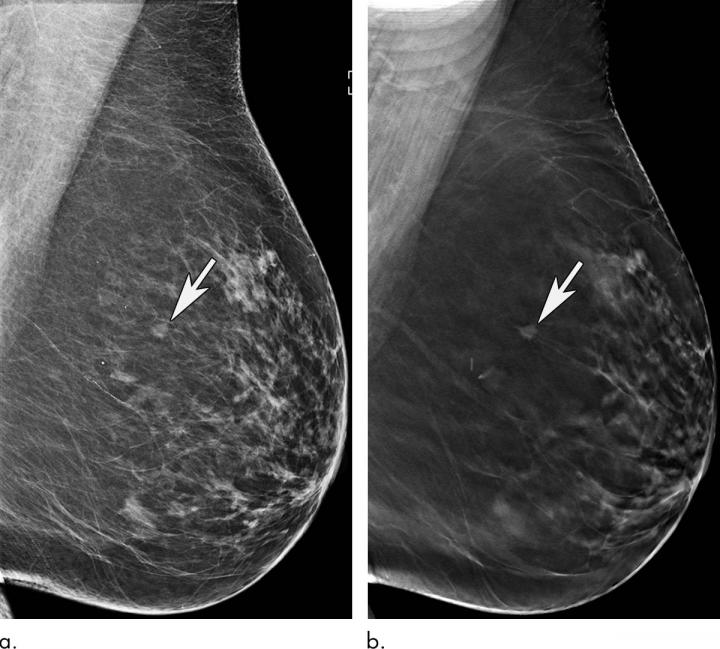

OAK BROOK, Ill. - Mammography remains an effective method for breast cancer screening in women ages 65 and older, with the addition of a 3-D technique called tomosynthesis improving screening performances even more, according to a study published in the journal Radiology .

Breast cancer is the most common cancer and the second most common cause of death from cancer among women in the United States. Research has shown that digital 2-D mammography (DM) is effective at reducing breast cancer-related mortality through early detection, when the cancer is most treatable. In 2011, the U.S. Food and Drug Administration approved tomosynthesis, also known as 3-D mammography, for breast cancer screening. Since then, it has become widely used as an adjunct to DM.

In the new study, researchers at Massachusetts General Hospital (MGH) sought to learn more about the performance of screening mammography in the older population and the added value of tomosynthesis. They compared screening mammograms from more than 15,000 women (mean age 72.7 years) who underwent DM with those of more than 20,000 women (mean age 72.1 years) who underwent tomosynthesis. Both approaches were highly effective at detecting cancer, but tomosynthesis had some advantages over the 2-D approach, including a reduction in false-positive examinations. Tomosynthesis also had a higher positive predictive value, the probability that women with a positive screening result will have breast cancer, and higher specificity, or the ability to distinguish cancer from benign findings, than DM.

"We've shown that screening mammography performs well in older women, with high cancer detection rates and low false-positives, and that tomosynthesis leads to even better performance than conventional 2-D mammography," said study lead author Manisha Bahl, M.D., M.P.H., radiologist at MGH and assistant professor of radiology at Harvard Medical School. "For example, the abnormal interpretation rate, which is the percentage of women who are called back for additional imaging after a screening mammogram, is lower with tomosynthesis than with conventional 2-D mammography. We also found that fewer cancers detected with tomosynthesis were lymph node-positive, suggesting that we are detecting cancers at an earlier stage. Detecting breast cancers at an early stage is the goal of screening mammography."